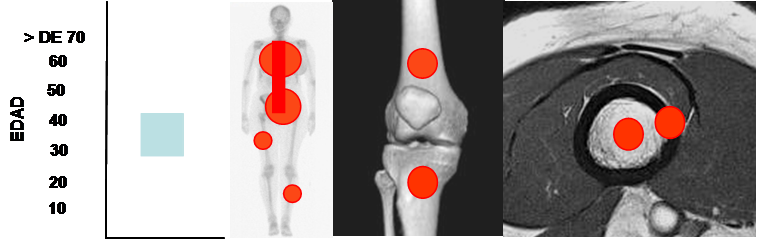

Fig 90. Condrosarcoma.

Mayor frecuencia entre la 4º y 5º década. Predominio en huesos largos, pelvis, columna y costillas. Lesión metafisodiafisiaria, de ubicación central o excéntrica.